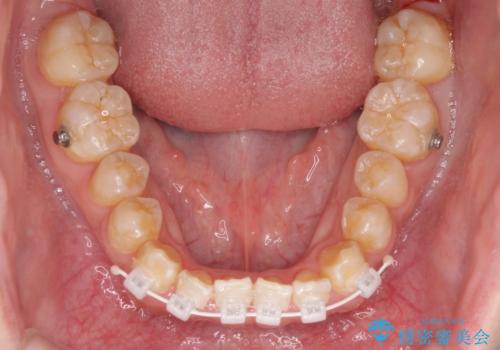

下顎前歯と上顎の部分矯正

- 矯正装置

- 審美装置

- 上下の前歯の叢生を気にして来院された患者様です。

前歯のみの矯正治療を希望でしたが、上顎臼歯が舌側転位していたため、上顎は全体を、下顎は前歯のみを矯正治療することとしました。